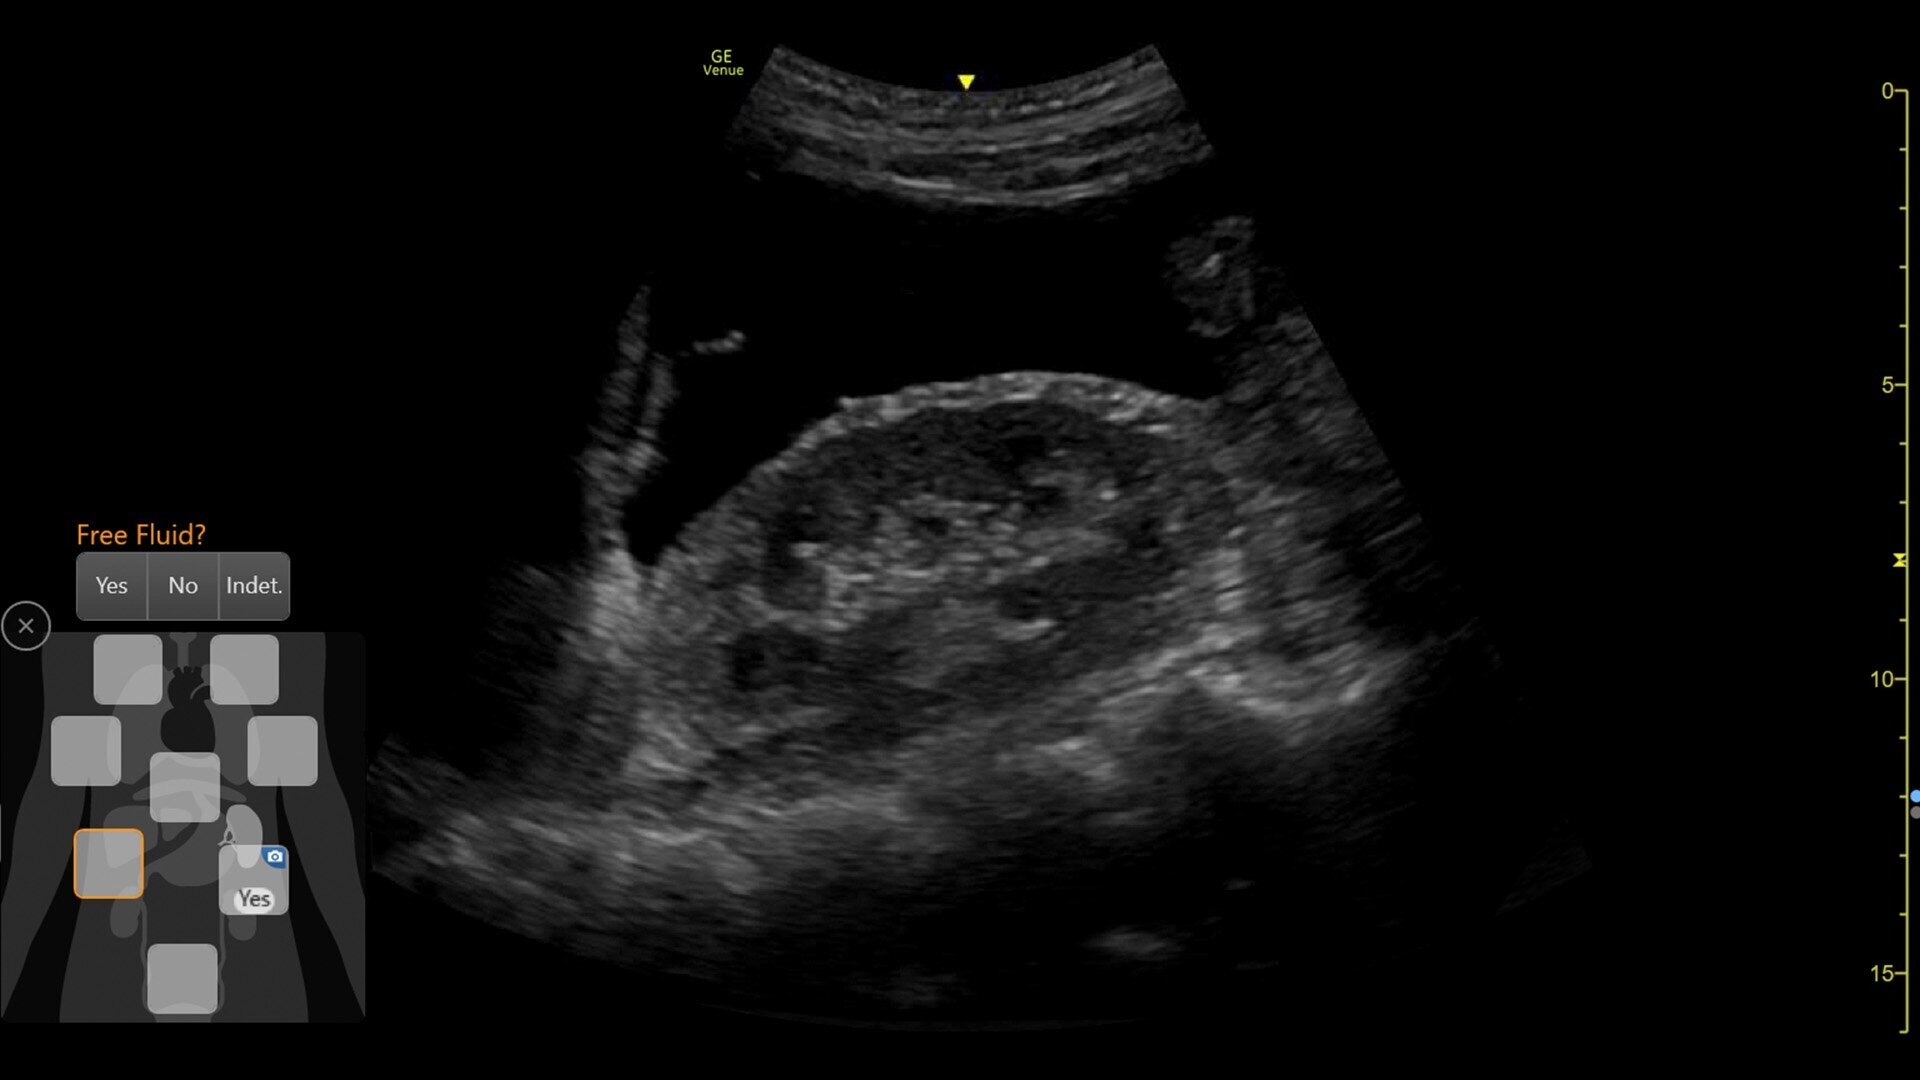

Automated tools

Simplify your workflow with AI-enabled clinical tools.

Helping drive consistency from user to user (whether one is an ultrasound novice or expert), Venue Fit features AI-enabled resources that help clinicians work smarter and more efficiently. Utilizing proprietary algorithms, we synthesize data from numerous patients to ensure accurate calculations for clinical confidence.